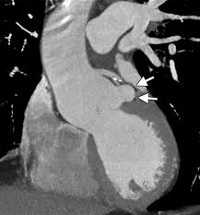

Предоперационное эхокардиографическое исследование выявило аневризму правого коронарного синуса с прорывом и формированием аорто-правожелудочковой фистулы, комбинированный аортальный порок с выраженным кальцинозом, тяжелым стенозом и недостаточностью, гипертрофию и дилатацию левого желудочка (конечный диастолический объем — 300 мл), снижение глобальной сократимости левого желудочка (фракция изгнания — 37%) на фоне диффузного снижения локальной, тяжелую трикуспидальную недостаточность, тяжелую легочную гипертензию. Порок сердца подтвержден данными МСКТ (см. рисунок). При КТ-коронароангиографии поражения коронарного русла не обнаружено. От проведения дооперационной терапии левосименданом мы вынуждены были отказаться по причине наличия у пациента частой желудочковой экстрасистолии и пробежек желудочковой тахикардии по данным мониторирования ЭКГ по Холтеру.

Аорто-правожелудочковая фистула (мультиспиральная компьютерная томография). ЛЖ — левый желудочек, Ао — восходящая аорта, ПЖ — правый желудочек, ЛС — легочный ствол. Стрелками обозначен диаметр аорто-правожелудочковой фистулы. Слева от фистулы визуализируется кальцинированный аортальный клапан.